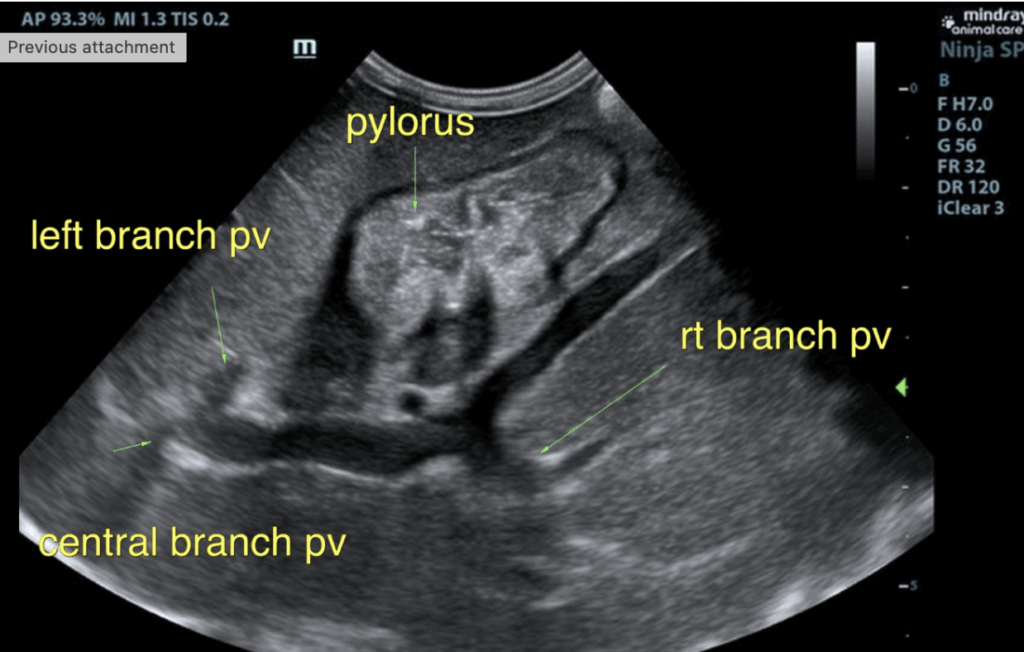

The liver was subnormal in size. The mid dorsal liver in this patient revealed an abnormal intrahepatic branch of the portal vein. This is most consistent with central divisional shunt. However, this should be further evaluated with CT. The gallbladder and common bile duct were unremarkable.

- Intrahepatic shunt – suspect central divisional or right divisional shunt

Intrahepatic shunts (IHPSS) are classified as left, central, or right divisional. IHPSS are more commonly seen in large or medium breed dogs.

- Central divisional IHPSS are described as a focal dilation of the portal vein forming a foramen with the caudal vena cava (CVC).